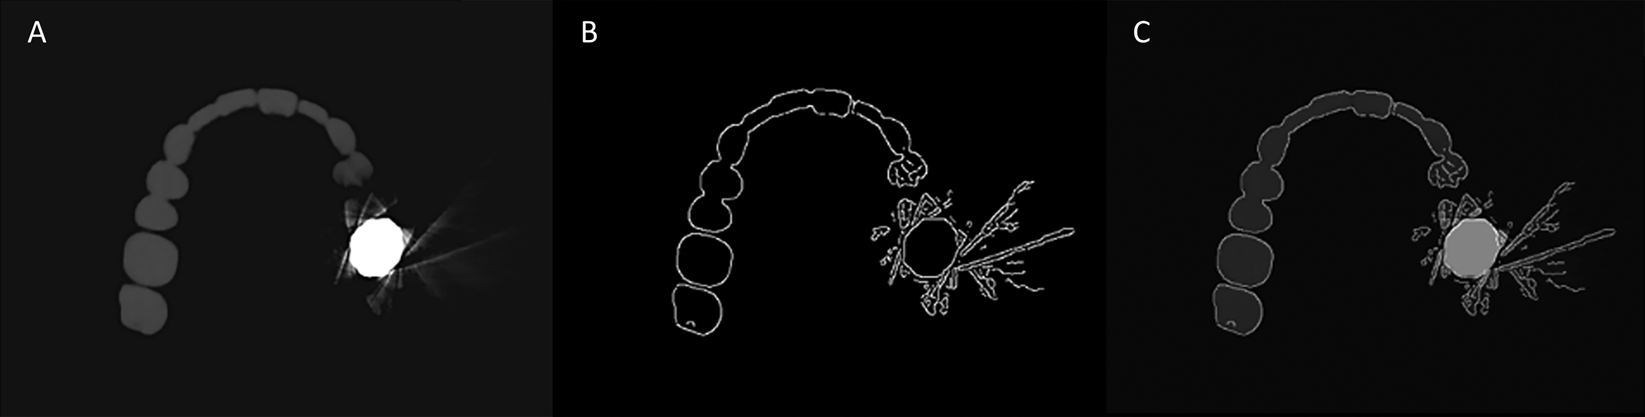

Figure 2

Auto-edge counting method by the application of the Canny edge detection algorithm on a CBCT image. The three images are the porcelain fused metal crown phantom obtained without the metal artifact reduction option. (A) Baseline image, (B) edge binary image using the Canny edge detection algorithm, and (C) superimposition of the edge binary image and baseline image. Note that the edge binary image well described the edge of the object in the baseline image.